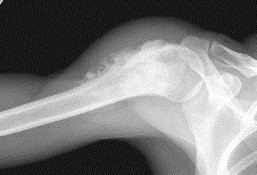

Рентгеновский снимок

Остеосаркома - это самая распространенная первичная злокачественная опухоль костей. Излюбленная локализация остеосаркомы - длинные трубчатые кости, особенно колена. Это заболевание чаще возникает у детей, подростков, а также у взрослых в возрасте около 30 лет. У больного появляются сильные боли, припухлость, которая может быть мягкой или твердой на ощупь. Юкстакортикальная остеосаркома - опухоль, исходящая из ткани надкостницы, также имеет злокачественный характер. Чаще всего она локализуется в подколенной впадине. Больного мучают постоянные, но несильные боли. На внешней поверхности кости можно нащупать твердое образование. Часто эти образования метастазируют, причем обычно метастазы возникают в легких (однако могут встречаться и в других органах, например, в печени).

Среди опухолей костей саркома Юинга обладает самой высокой степенью злокачественности. Она характеризуется быстрым ростом и метастизированием. Возникает преимущественно у детей и молодых людей. Саркома Юинга образуется из костной ткани. Она может поразить любую кость однако чаще всего локализуется в области таза и плеча откуда метастизирует в другие кости и легкие. Первые симптомы саркомы Юинга аналогичны симптомам остеомиелита. У больного возникают боли которые в скором времени проходят, отмечается незначительное повышение температуры и лейкоцитоз.